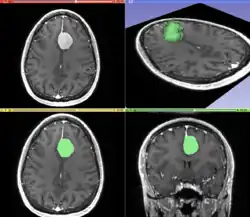

Image and sound processing

Information can take the form of images, sound, video or other multimedia. Bits of information can be streamed via signals. Its processing is the central notion of informatics, the European view on computing, which studies information processing algorithms independently of the type of information carrier – whether it is electrical, mechanical or biological. This field plays important role in information theory, telecommunications, information engineering and has applications in medical image computing and speech synthesis, among others. What is the lower bound on the complexity of fast Fourier transform algorithms? is one of the unsolved problems in theoretical computer science.

| FFT algorithms | Image processing | Speech recognition | Data compression | Medical image computing | Speech synthesis |